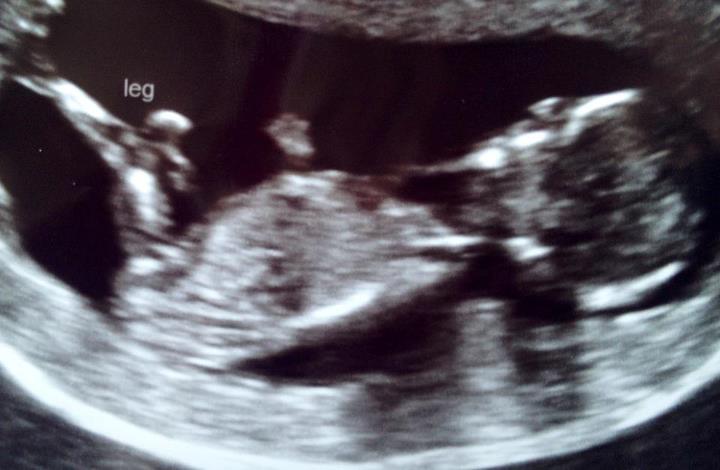

SECOND image WAS perfect but baby kicked legs out and turned the head toward my spine! U can see the neck and an ear...also a hand or foot up top. I think the nub is okay here??? Doc wouldn't work with me on a good shot. He said the scan wasn't about gender :( the nurse was trying but doc was rushing.

Attachment 3949